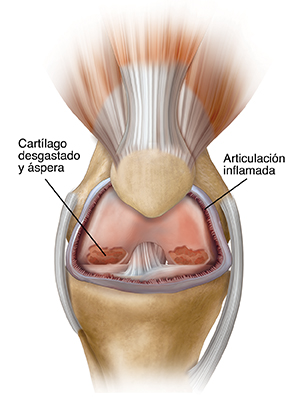

El motivo más común para hacer la cirugía de reemplazo de rodilla es la artrosis. Es una enfermedad de las articulaciones por desgaste que afecta a la mayoría de los adultos de mediana edad y mayores. La artrosis causa la desintegración del cartílago articular y luego de los huesos de las rodillas.

Otras formas de artritis también pueden causar la degeneración de la articulación de la rodilla. Por ejemplo, la artritis reumatoide y la artritis causada por una lesión en la rodilla. Las roturas (fracturas), los desgarros del cartílago o los desgarros de los ligamentos también pueden causar daños permanentes en las rodillas con el tiempo.

| Articulación de rodilla con artritis. |